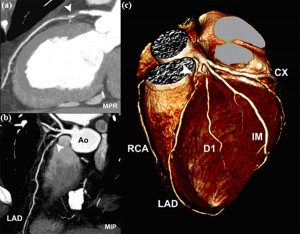

Resonancia magnetica cardiovascular corazón. La resonancia magnética cardiaca (RMC) es un una técnica de imagen para el estudio no invasivo del corazón, inocua ya que no utiliza radiación, bien tolerada y segura. Actualmente se encuentra disponible en la mayoría de hospitales. Permite estudiar en una sola exploración la función y estructura del corazón. Ofrece una imagen detallada del corazón, incluidas las cavidades y las válvulas. Está indicada para el estudio anatómico y funcional de cardiopatías congénitas, el origen anómalo de las coronarias, estudio de viabilidad y de perfusión del músculo cardiaco (con administración de contraste), estudios de función ventricular, estudio de miocardiopatías (enfermedades del músculo cardiaco), enfermedades del pericardio (capa de tejido que recubre al corazón) y masas cardiacas.

Una resonancia magnética proporciona imágenes detalladas del corazón y los vasos sanguíneos desde múltiples planos. Con frecuencia, se emplea cuando se necesita más información después de que a usted le han hecho una ecocardiograma o una tomografía computarizada del corazón.